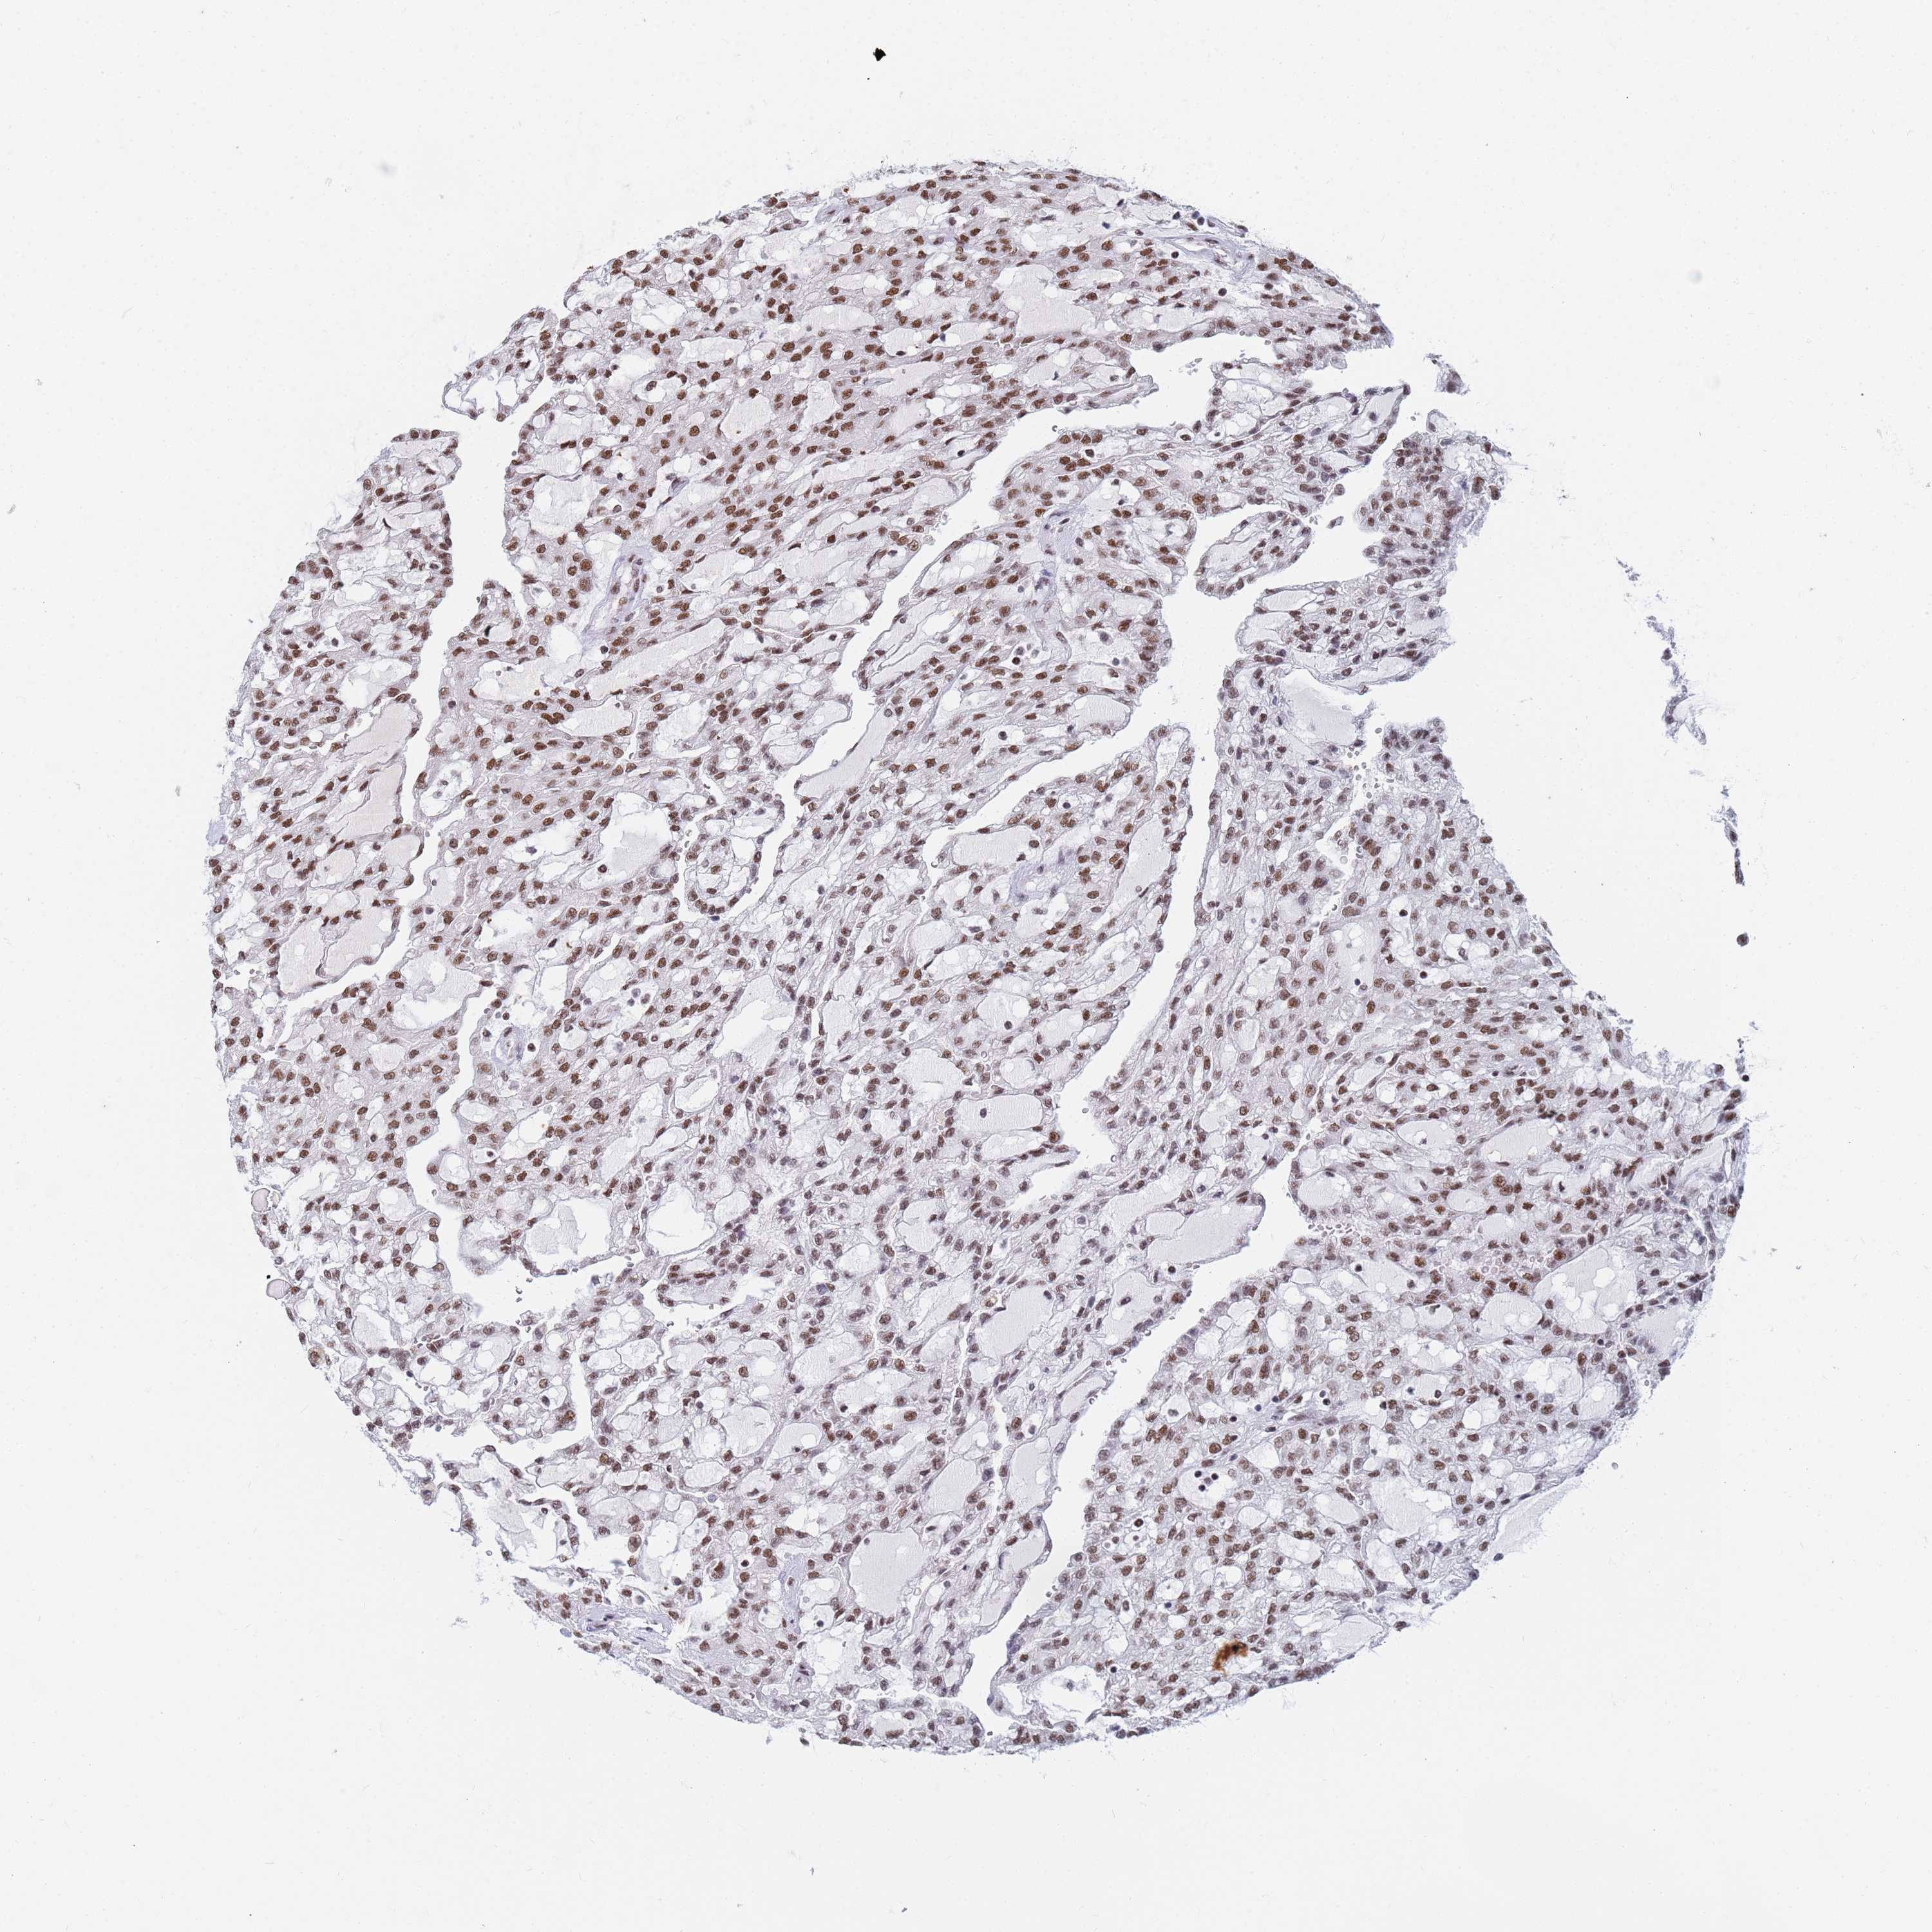

CANCER RENAL CANCER Show tissue menu

KICH TCGA KIRC TCGA KIRC VALIDATION KIRP TCGA PROTEIN RCC CPTAC PROTEIN EXPRESSION